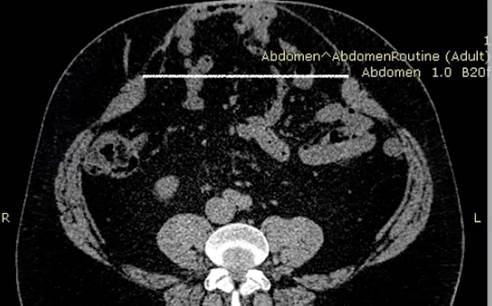

Данные компьютерной томографии (КТ) приведены на рис. 2.

Рис. 2. КТ брюшной полости первого пациента перед операцией.

Белой линией обозначены грыжевые ворота